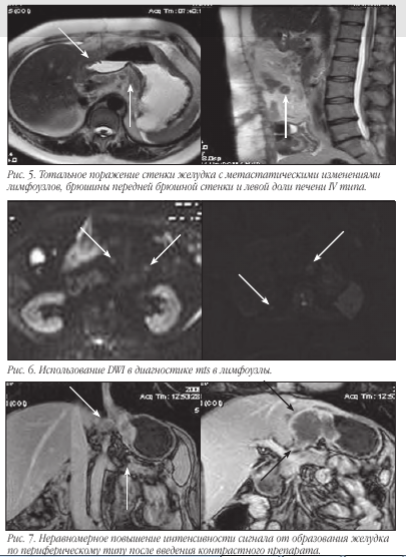

В связи с тем, что визуализировать достоверно все слои стенки желудка чаще всего не представляется возможным, то критериями ее поражения являются степень утолщения и протяженности изменений. При поражении всех слоев и распространении процесса за пределы серозы основными МР-признаками следует считать нечеткость и размытость наружного контура стенки желудка, снижение сигнала от перигастральной жировой клетчатки. В современной лучевой диагностике МРТ применяется для определения стадии по N и M стадиям, используя TNM классификацию. Мы в своей работе используем классификацию Японской ассоциации по раку желудка. В основе классификации JGCA (1998) лежит анатомический принцип. В отличие от принципов JGCA, классификация UICC (Международного противоракового Союза 2002) рассматривает лишь количественное поражение регионарных лимфатических узлов вне зависимости от их локализации.

Метастатическое поражение лимфоузлов, печени и брюшины - N, H и P.Основными признаками поражения стенок желудка являются: утолщение стенки более 5 мм, неровность и бугристость контуров, изменение МР-сигнала от образования, распространение за пределы стенки.

После введения контрастного препарата «Магневист» определяется неравномерное повышение интенсивности сигнала от образования желудка по периферическому типу.

Визуализируется поражение не только брюшного отдела пищевода, но и дистальной трети его грудной части с признаками стеноза.